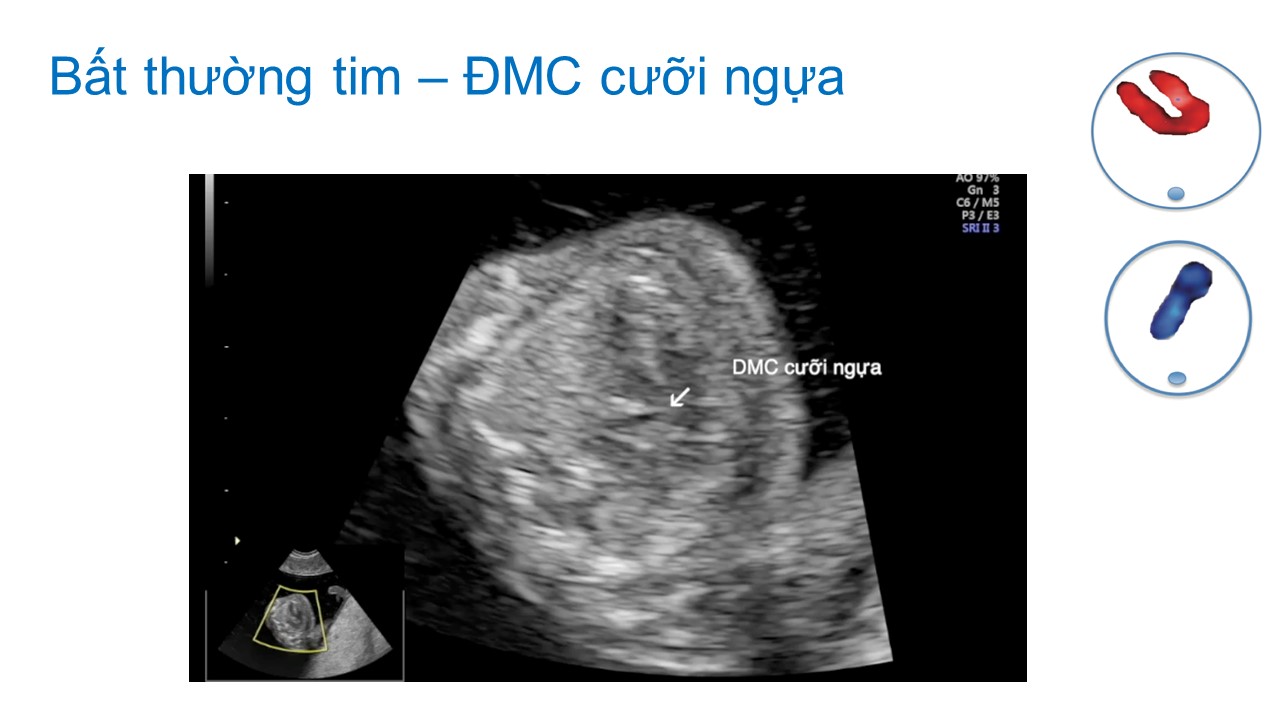

Siêu âm hình thai học quý I